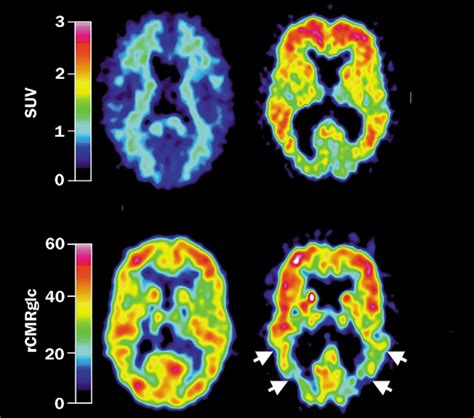

The images obtained from the PET scan are analyzed by a radiologist or a nuclear medicine specialist. The presence and distribution of amyloid plaques are assessed, providing valuable information about the patient's condition.

Interpreting Amyloid PET Imaging Results

The results of Amyloid PET Imaging are typically reported as either positive or negative for amyloid plaques. A positive result indicates the presence of amyloid deposits, which is often associated with Alzheimer's disease. However, it is important to note that a positive result does not confirm a diagnosis of Alzheimer's disease; it merely indicates the presence of amyloid plaques, which can also be found in other conditions.

A negative result suggests the absence of significant amyloid deposits, which can help rule out Alzheimer's disease as the cause of cognitive impairment. However, a negative result does not exclude the possibility of other forms of dementia or neurodegenerative diseases.